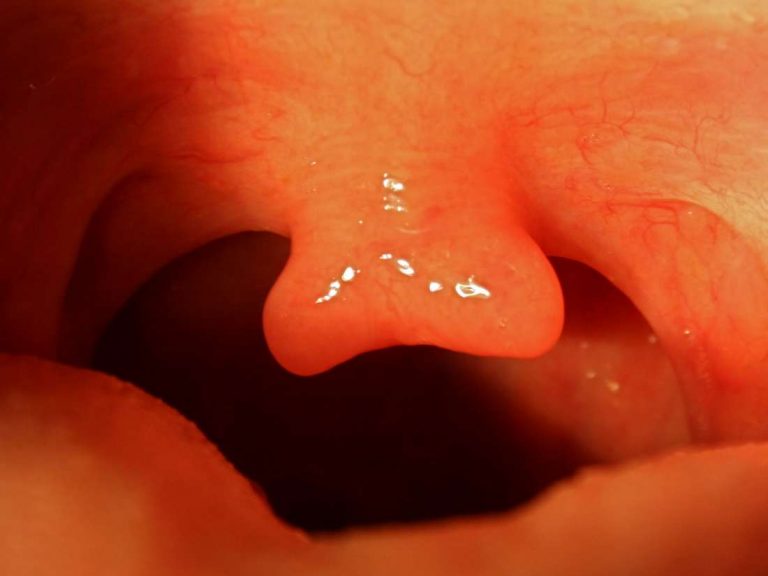

A look at bifid uvula, a condition affecting the palate of the mouth. Included is detail on complications of the condition and outlook for a bifid uvula.